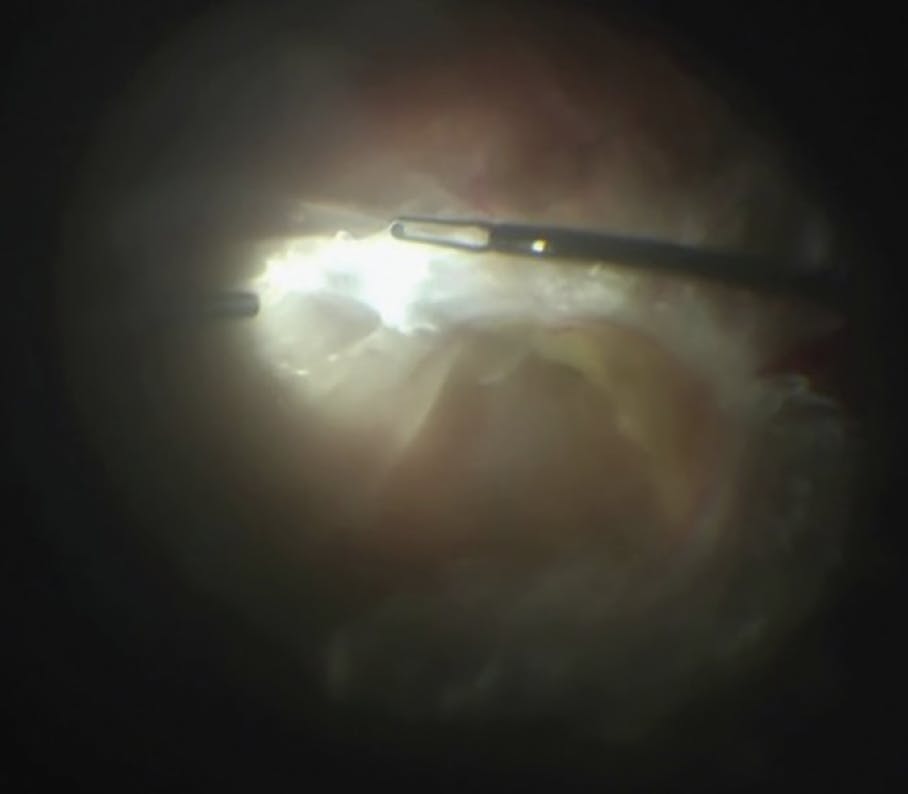

The plane of dissection is always the preretinal and sub-fibrous membrane space. Respecting this plane and selecting instruments to best achieve safe dissection is paramount to avoid iatrogenic breaks. Fortunately, most diabetic membranes are not tightly and contiguously attached to the retina. Instead, they have strong focal attachments with intervening clear areas (Figure 1). These areas can be identified and exploited to efficiently segment and remove even broad areas of fibrosis. Before segmentation, I like to use forceps to dynamically examine the membranes. By gently lifting and reflecting over the edges, I can examine the underside of membranes and identify accessible areas to advance the dissection (Figure 2).

<p>Figure 2. Preretinal membranes can be gently retracted to inspect for the open area. Dynamic manipulation of membranes can be very helpful to interrogate unique vitreoretinal relationships unique to the TRD and allow safer dissection.</p>

Figure 2. Preretinal membranes can be gently retracted to inspect for the open area. Dynamic manipulation of membranes can be very helpful to interrogate unique vitreoretinal relationships unique to the TRD and allow safer dissection.